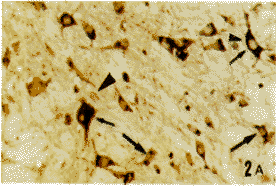

图2A 延髓上段网状结构mGluR1和ER双重免疫组织化学染色切片。图2B为A的相邻连续切片,IL-2免疫组织化学染色。各种箭头和三角所指同图1 ×100

Fig.2 A mGluR1 and ER double immunohistochemical staining section of the reticular formation of upper medulla oblongata.B:IL-2 immunohistochemical staining serial neighbor section of A., The targets pointed by different arrows and triangles are the same as in Fig.1. ×100

在大鼠大脑皮质、延髓和脊髓颈、胸、腰段均可见到mGluR1,ER和IL-2免疫反应性神经细胞。mGluR1免疫反应产物为蓝黑色,位于胞膜;ER免疫反应产物为棕褐色,位于胞浆或核内。IL-2免疫反应产物亦为棕褐色,位于胞浆内。在大脑皮质,上述3种阳性细胞分布于皮质各层,以第Ⅴ层最为密集。在数量上,mGluR1阳性细胞最多,ER阳性细胞次之,IL-2阳性细胞最少。阳性细胞以锥体形大、中细胞为主(图1A,B)。在延髓和脊髓,mGluR1和ER阳性神经元的分布已述于我们的另一篇文章[8],主要分布于迷走神经背核、孤束核、三叉神经脊束核和网状结构及脊髓的腹角、背角和中间带,以mGluR1阳性神经细胞占优势,以上细胞以中等大多角形细胞为主(图2A,3A,4A)。IL-2阳性细胞在延髓和脊髓的分布均较上述两种细胞少(图2B,3B,4B),但分布类型相似。本实验主要对大脑皮质、延髓网状结构和脊髓腹角的含上述免疫、神经、内分泌3类物质的细胞进行研究。在mGluR1和ER双重染色的切片上,可见3种细胞:(1)mGluR1单标细胞,胞膜为蓝黑色;(2)ER单标细胞,胞浆或胞核呈棕褐色;(3)mGluR1/ER双标细胞,胞膜为蓝黑色,胞浆和胞核为棕褐色。双标细胞约占全部(单+双)标记细胞的50%~60%(依部位而异,图1A,2A,3A,4A)。双标细胞的形态主要为锥体和多极细胞。通过对相邻两张切片的投影核对,证实在大鼠大脑皮质、延髓网状结构和脊髓腹角内存在mGluR1/ER/IL-2三重标记细胞,即同一神经细胞既为mGluR1/ER阳性,又呈IL-2阳性,1个细胞在相邻两张切片上的影像重迭(比较图1A与1B,图2A与2B,图3A与3B,图4A与4B)。三标细胞约占mGluR1/ER双标细胞总数的30%。